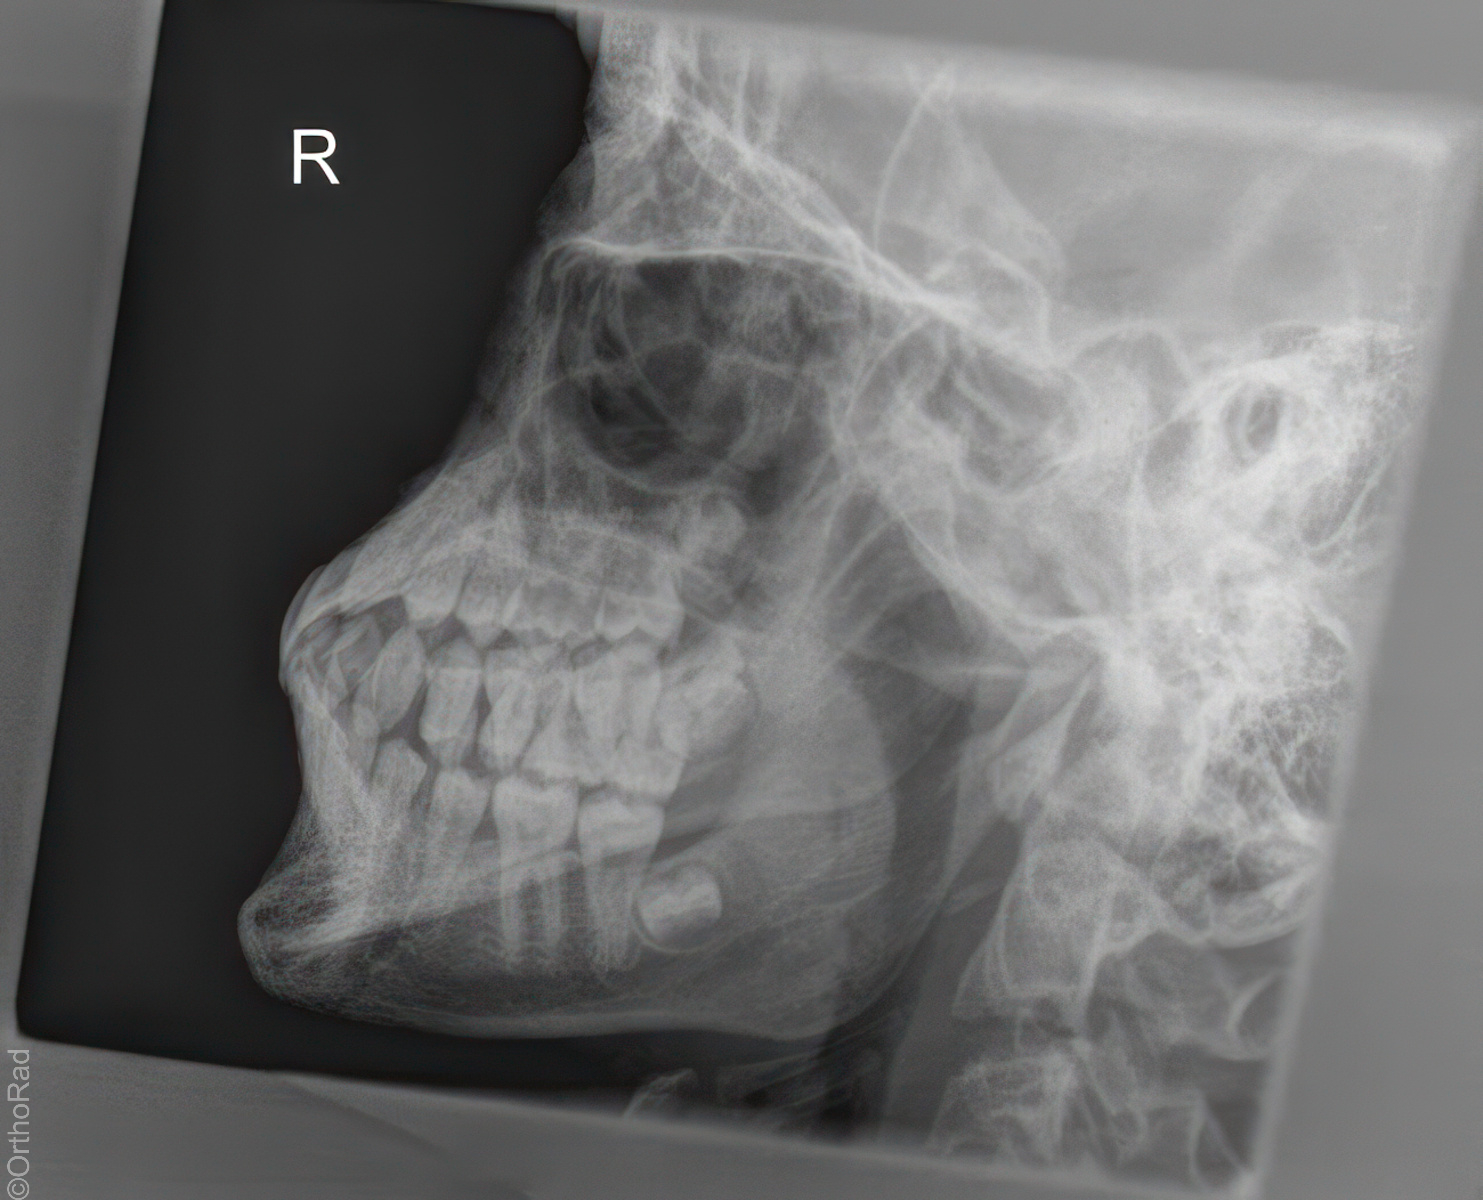

Isolierter Unterkiefer nach Eisler

Lagebestimmung retinierter Zähne oder Geschwülsten, bei Frakturen, Suche nach Herden (Foci) an der Zahnwurzel.

Lagerung

Seitenlage

liegt auf steifer Schulter

Detektor mit 2 x 15° Keilen (30°) schräg unterpolstern, so dass der Kopf abhängt

Schläfe liegt dem Detektor an

Unterkiefer wird vorgestreckt, Mund leicht geöffnet

leichte Drehung nasalwärts zum Detektor

Zentralstrahl

Abhängig von der Kopfneigung, zielt im Winkel von ca. 10° bis 15° caudo-cranial auf detektornahen Unterkiefer in die ertastete Backengrube (oder unterhalb des detektorfernen Unterkieferwinkels)

Qualitätskriterien

Der detektornahe Unterkieferast stellt sich bis zum Kiefergelenk frei dar.